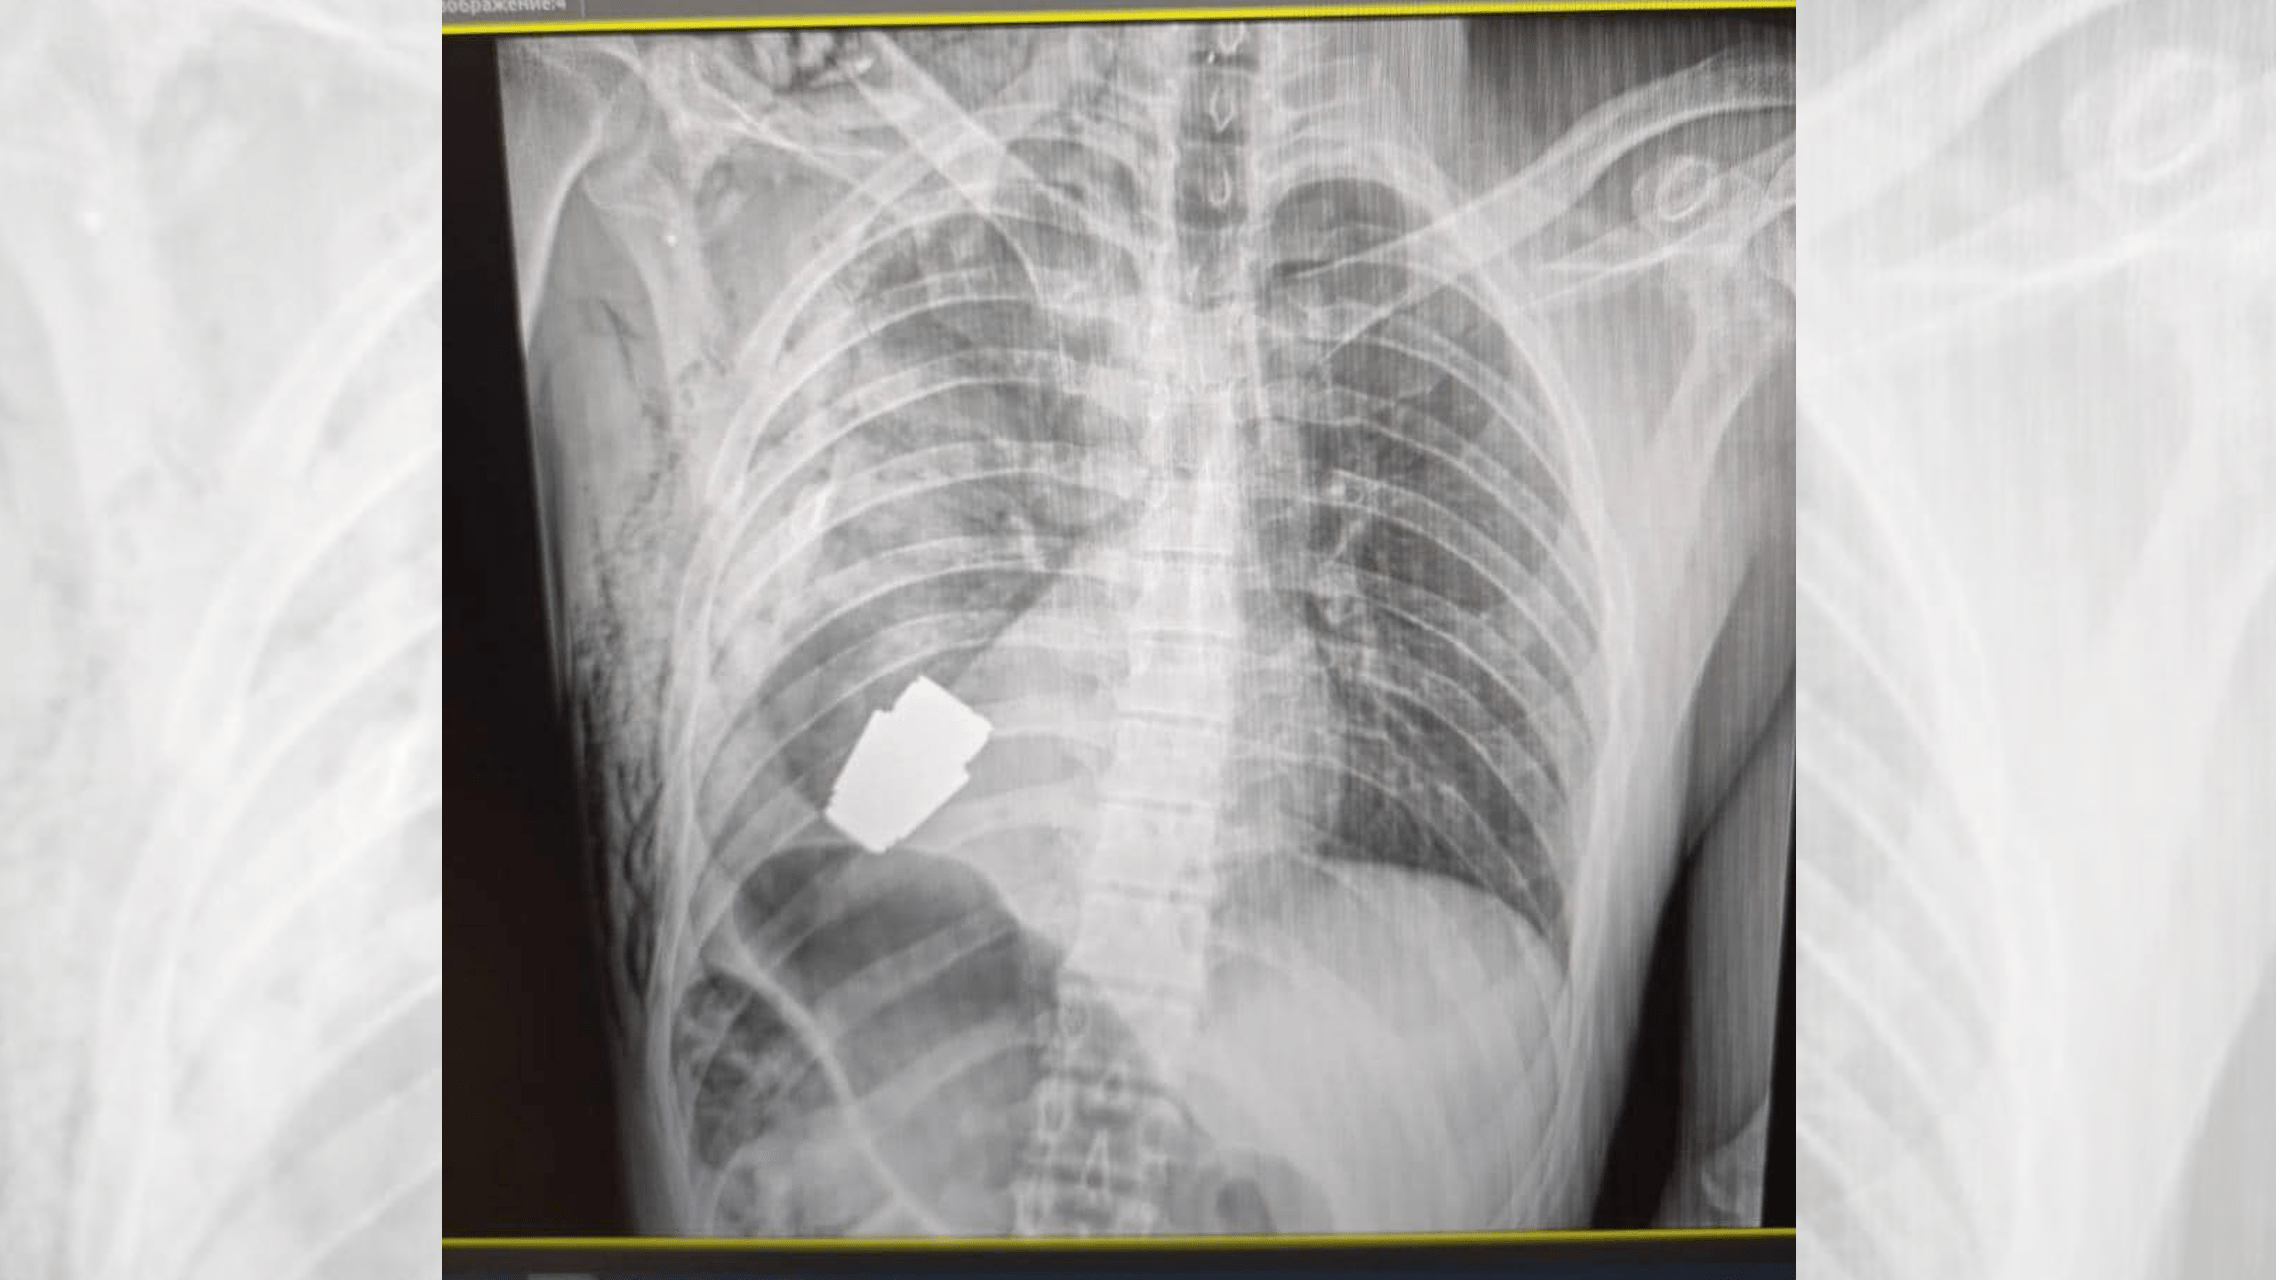

On Jan. 9 , Hanna Maliar , Ukraine ’s deputy minister of defense mechanism , posted an ecstasy - ray imageon Facebookshowing the unexploded ordnance lodged inside the chest of a Ukrainian soldier .

An X-ray image of the unexploded grenade, lodged just below the soldier’s heart.

Maliar wrote that Andrii Verba , one of the most experient surgeon in Ukraine ’s armed forces , extend out the mathematical process , and that he was assisted by two sappers , or combat engineers , to protect aesculapian staff and verify the operation was done safely . Alongside the patientX - ray , Maliar ’s station shows Verba holding the grenade after it was removed . VOG grenades are around 1.6 inches ( 4 centimeters ) long and can be arouse from grenade launcher as far as 0.2 stat mi ( 400 meters ) from a target , harmonise tothe BBC .

" The undischarged part of the grenade was take from under the warmheartedness . The grenade did not break loose , but remained volatile , " wrote Anton Gerashchenko , Ukraine ’s internal social function ministerial adviser , in an update onTelegram(translated from Ukrainian ) . He say that the patient is about 28 years old and is undergoing further renewal and retrieval .